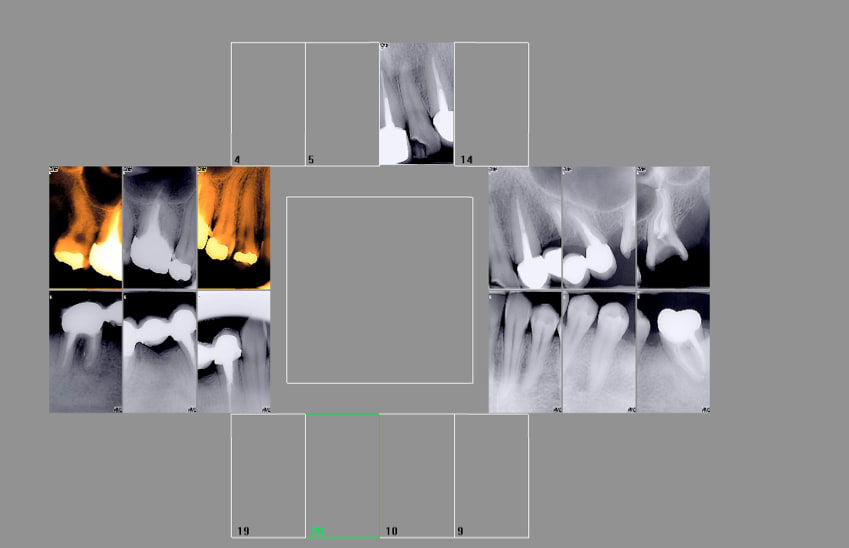

Historique de la 17 de ma femme.

Tu as raison des fois on y peut rien. J'aurais du l'extraire. -))))

Avec plaisir. 2004 ( c'était une patiente lambda) Et 2016......

Elle n'a rien payé. Mauvais exemple de responsabilisation.

Ceci dit si je lui avais enlevé toutes ses dents au départ et fait un complet à la casa ( meme correctement réalisé) je pense que nous ne serions pas passés devant monsieur le maire. -)))